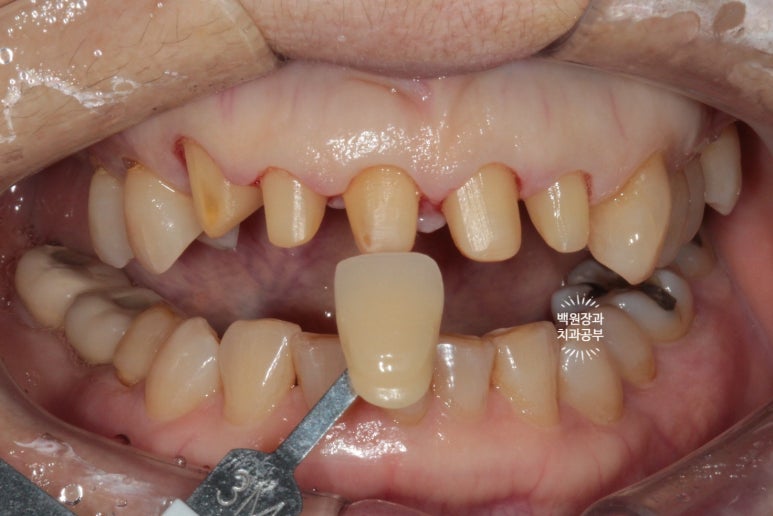

확실히 가지런해진 모습인데요, 인위적으로 색상이 밝은 것 같다고 다른 치아와 유사한 색상으로 만들어 싶어하셨어요.

음.. 대부분의 환자들이 보통 앞니 크라운 치료시 보다 밝은 색상을 원하시는데, 치과의사가 좋아하는 정확한 내 치아색을 원해하셔서 조금의 수정을 해보기로 하였습니다.

짜잔~ 조금의 차이점이 느껴지시나요?

치아의 목부분 (치경부)의 색상이 약간 yellowish하게 수정되었습니다.

보다 더 자연스러운 느낌이에요!